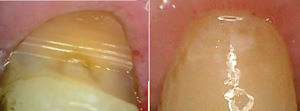

Keilförmige Defekte sind die häufigsten Zeichen von Bruxismus und wie ein kleiner Spiegel der Seele.

Mit kleinen Retentionsgrübchen kann man das Komposit besser retinieren. Der Bruxismus bewirkt in vielen Fällen nach 10-20 Jahren einen zweiten keilförmigen Zahnhalsdefekt unter der Zahnhalsfülung.